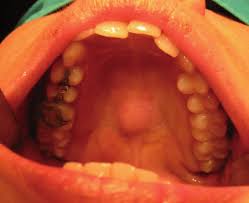

- Lesión benigna conocida como adenoma

El diagnostico pienso debería hacerse en principio a través de un buen examen físico, observación y si es necesario biopsia (la toma de una pequeña muestra de la masa) para tener el origen correcto y dar el tratamiento indicado. Si se trata de cualquiera de estos cuadros anteriores que hemos visto, cabe la posibilidad de que sea necesario extirparlo mediante una sencilla cirugía, pero también existen productos para tratar estos casos.

Los médicos proponen acudir a un medico o cirujano maxilofacial para una evaluación correcta que no deje lugar a dudas.